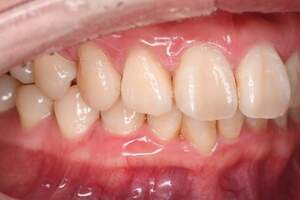

歯石除去

治療前

治療後

| 年齢 | 43歳・男性 |

| 主訴 | 歯石をとりたい |

| 治療内容 | 歯石除去 |

| 治療期間 | 30分 |

| 費用 | 約2,000円 |

| リスク・副作用 | ・歯ぐきの炎症が強いと歯石を取る際に出血することがあります ・処置後に歯がしみることがあります ・歯と歯の間に隙間ができるので、息が漏れ発音しにくいと感じることがあります ・歯ぐきの炎症が軽減すると歯ぐきが引き締まり、歯が長く見えることがあります |